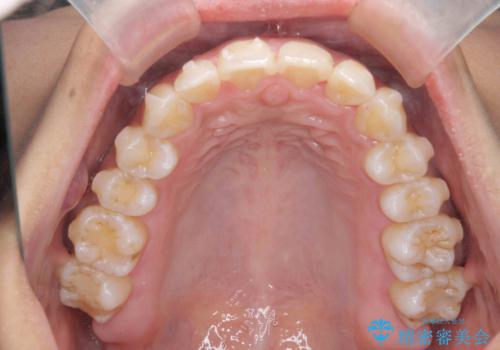

出っ歯感のある前歯を治したい、抜歯をしないマウスピース矯正

- 前歯のガタつき、突出感のある前歯の改善を求めて来院されました。

前歯の角度を改善し審美性を高めるとともに、奥歯のガタつきも並べ直すことで安定した咬合関係の確立を目指します。

歯列の側方拡大をしっかりと行ったことで歯を抜かずに前歯の角度をしっかりと改善することができました。